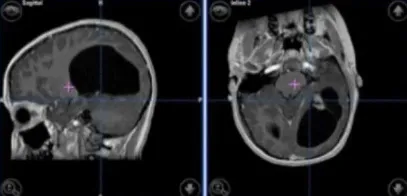

十三岁的女孩,身体一直很健康。两年多来,她持续感觉头晕、浑身没力气,记忆力明显下降,脾气也变得越来越暴躁。家长带她到Rutka教授所在的医院就诊,核磁共振检查发现左枕叶有肿瘤占位,考虑为毛细胞性星形细胞瘤。

手术由Rutka教授亲自主刀。团队借助术中神经导航,并采用无框架立体定向技术,精准定位并完整切除了肿瘤。